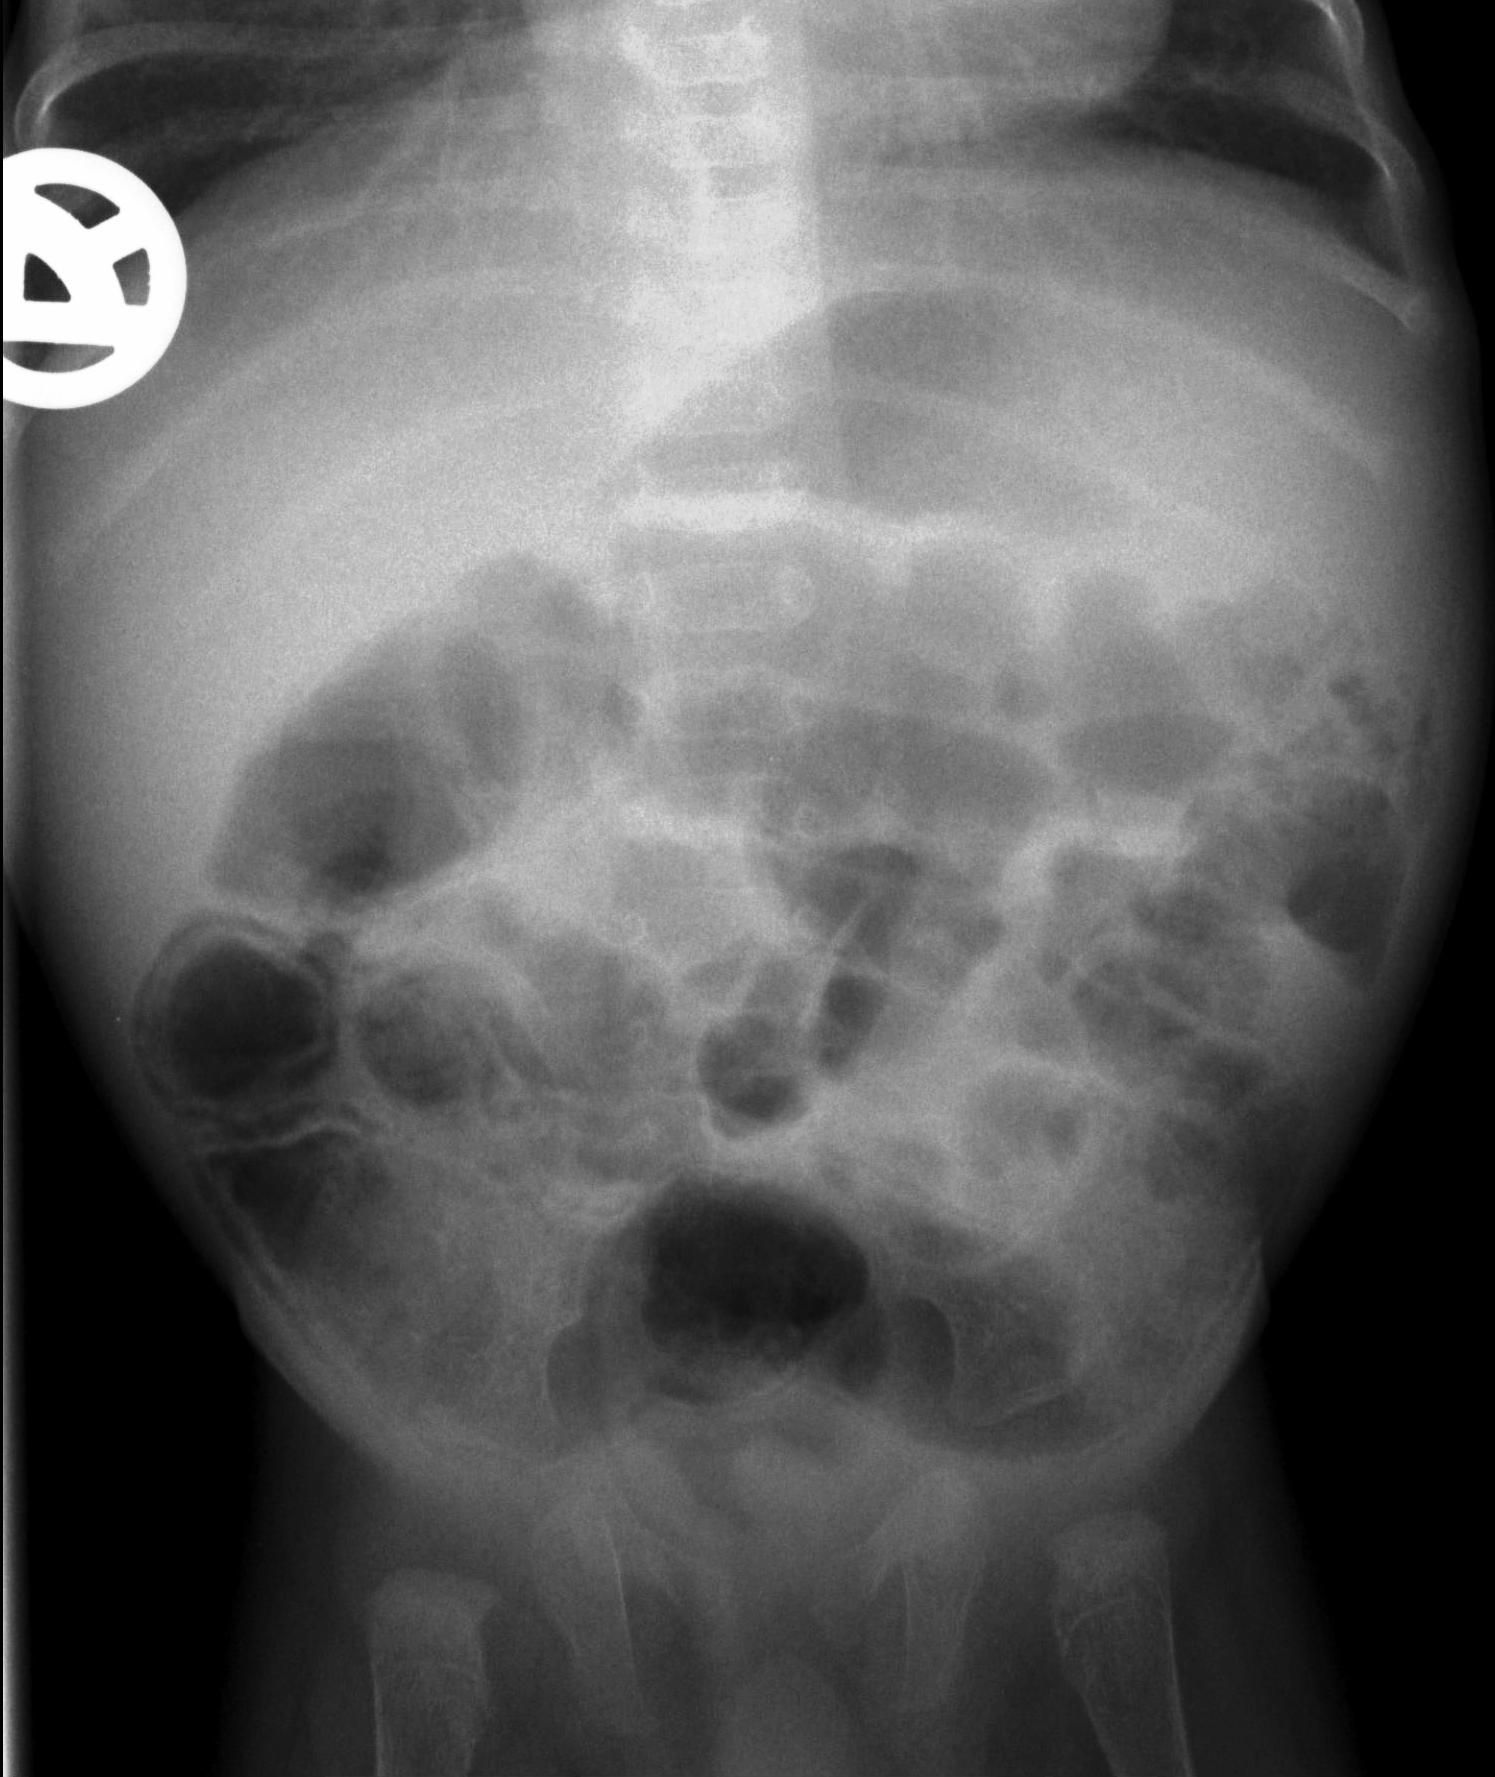

Necrotizing enterocolitis (NEC). It is a severe intestinal necrotizing disease of the newborns. It usually occurs as early as the first 10 days of life, but can happen in the first few months after birth. Vomiting, distended intestines, bloody stool, acidosis, peritonitis and perforation are frequent findings. Plain abdominal X-ray can be non-informative in the early stages of the disease; later distension indicates the separation of loops due to wall thickening. Often, air bubbles appear in the intestinal subserosal or submocosal layers, as characteristic signs of “intestinal pneumatosis”. The intramural air can diffuse to the mesenteric veins and appear in the portal circulation in the projection of the liver. Free abdominal air is indicative of perforation and requires surgical intervention. US examination can reveal these characteristics of the disease before X-ray is indicative. US can depict thickened intestinal wall, portal and intramural air, abdominal free fluid or abscesses.

19. Distended bowel loops. Air is seen in the intestinal wall, intestinal pneumatosis. Necrotizing enterocolitis.